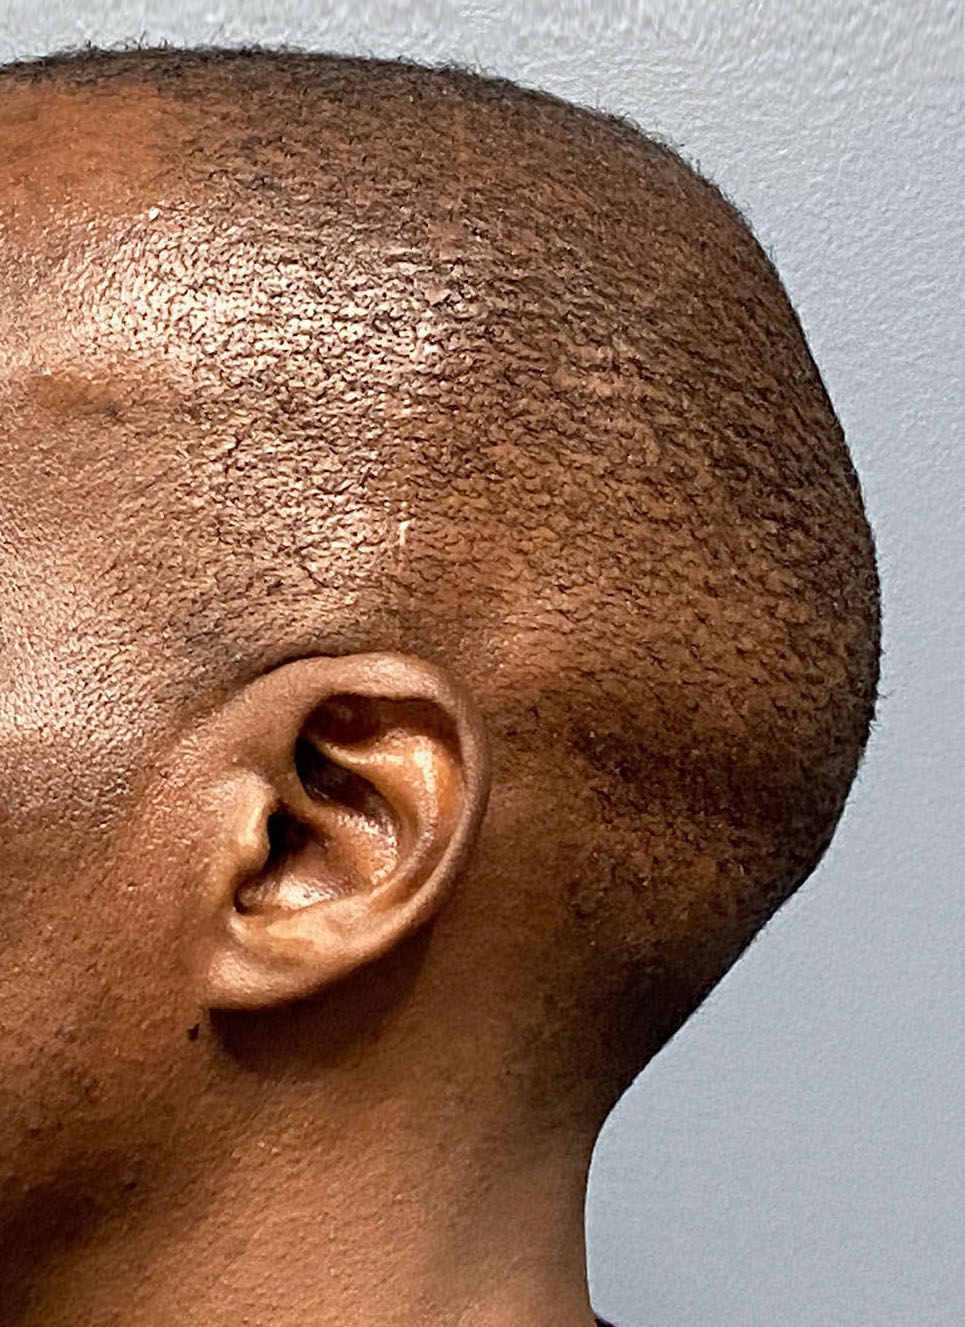

Desire for reshaping of an asymmetric flat back of the head in a shaved head male.

A combined back of the head reshaping procedure was done with a custom skull implant, sagittal ridge reduction and a right temporal muscle reduction.

Desire for reshaping of an asymmetric flat back of the head in a shaved head male.

A combined back of the head reshaping procedure was done with a custom skull implant, sagittal ridge reduction and a right temporal muscle reduction.